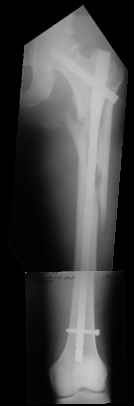

Re: Severely comminuted Trochenteric #

I would use a small wire distractor mentioned in the list some times. Proximal wire is in the iliac crest in AP direction. The leg is adducted. I attached some images. At the AP view under image intensifier you can see adduction but even slight valgus reduction.